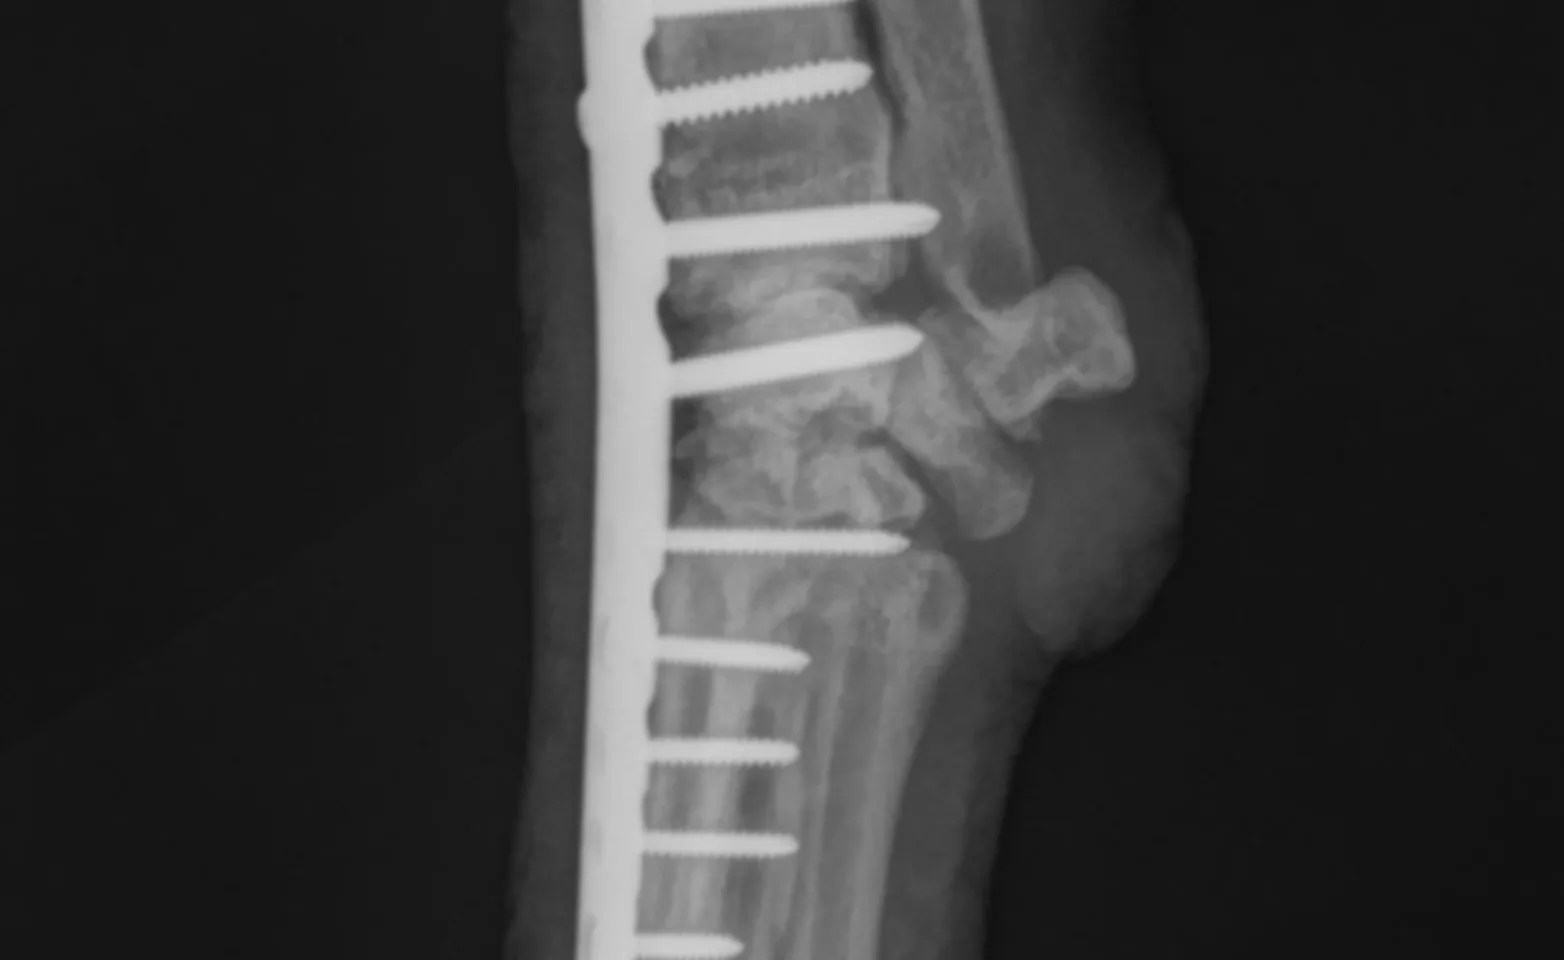

Pantarsal and partial tarsal arthrodesis